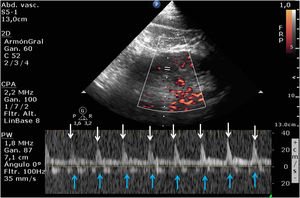

Varón de 86 años ingresado en UCI por insuficiencia cardíaca derecha (ICD) secundaria a comunicación interauricular tras implante de Mitraclip®, hipertensión pulmonar crónica grave, fracaso renal agudo y elevación de transaminasas y bilirrubina. Se realizó VExUS (Venous Excess Ultrasound Score). La figura 1 muestra la inversión del flujo durante la sístole ventricular en el doppler de venas suprahepáticas (flecha roja). La figura 2, el patrón venoso interlobar renal monofásico (ausencia de flujo venoso [flechas azules] en la sístole [flechas blancas]). Ambos hallazgos son sugestivos de congestión venosa sistémica (CVS) grave. Sin embargo, el doppler de vena porta (DVP) (fig. 3) no fue pulsátil (como se esperaría en la CVS). La fibrosis portal por cirrosis (secundaria a ICD) impide la transmisión de pulsatilidad en el flujo venoso, siendo el DVP, en este caso, no valorable dentro del VExUS para el diagnóstico de CVS, por tratarse de un resultado falso negativo.